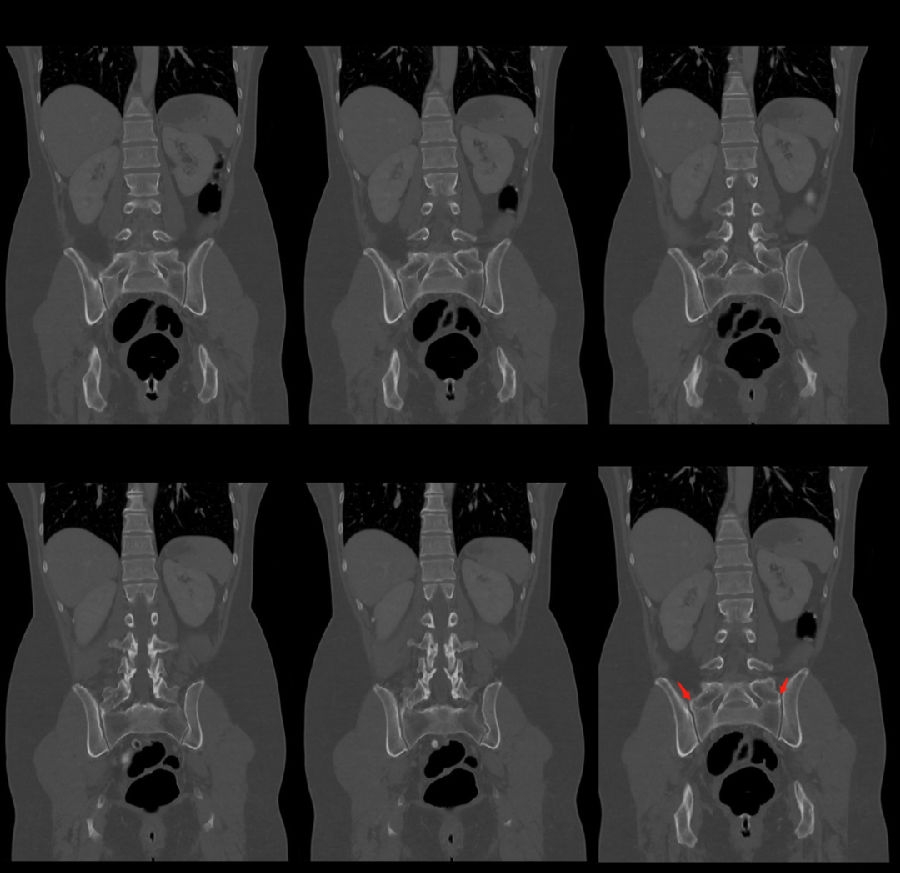

腰椎骶化及骶椎腰化均是椎骨发育的异常,腰椎骶化是指第五腰椎外型类似骶椎形态,并构成骶骨块的一部分,一侧或两侧横突肥大呈翼状,与骶骨发生融合或形成假关节。骶椎腰化是指第一骶椎演变成腰椎样形态,即第一骶骨从筋骨块中游离出来形成第6个腰椎。

目前,腰骶移行椎以Castellvi的分类方法最为常用。其主要根据横突形态及其与骶骨、髂骨是否融合或形成假关节而分为4型,Ⅰ、Ⅱ、Ⅲ型又根据单、双侧分为A、B两个亚型。

I型:主要为腰5横突发育不良,横突宽度大于19mm,并将其分为两个亚型Ia(单侧横突发育不良)或Ib(双侧横突发育不良)

L5右侧横突肥大,为Ⅰa型

L5双侧横突肥大,为Ⅰb型

II型:表现为不完全的腰椎骶化,具有增宽的横突,并且和骶骨形成假关节,并将其分为两个亚型IIa(单侧关节形成)或IIb(双侧关节形成)

L5左侧横突肥大,假关节形成,为Ⅱa型

L5双侧横突肥大,假关节形成,为Ⅱb型

III型:单侧(IIIa)或双侧(IIIb)腰椎完全骶化,腰5横突与骶骨完全骨性融合

L5右侧横突肥大与骶骨发生骨性融合,为Ⅲa型

L5双侧横突与骶骨骨性融合,为Ⅲb型

IV型:一侧为II型即腰5横突与骶骨形成假关节,对侧为III型即腰5横突与骶骨形成骨性融合

IV型即混合型:L5双侧横突肥大,一侧与骶骨相接触为Ⅱ型表现,另一侧与骶骨形成骨性融合为Ⅲ型

它与腰骶部疼痛存在密切的相关性是不可忽视的并干扰诊断与之症状相近的其它疾病如椎间盘突出、致密性骨炎、强直性脊柱炎等等当然这其中有些疾病可以并存X线、CT检查在腰骶部移行椎的诊断中有重要意义不仅能对本病做出诊断并且有助于鉴别诊断。